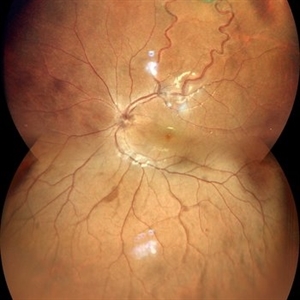

Familial Exudative Vitreo-retinopathy

Color photo montage of 21-year-old male with familial exudative vitreoretinopathy in an amblyopic eye.

Photographer: Dr. Akansha Sharma-Retina Foundation, Ahmedabad

Condition/keywords: familial exudative vitreoretinopathy (FEVR), retinal ischemia